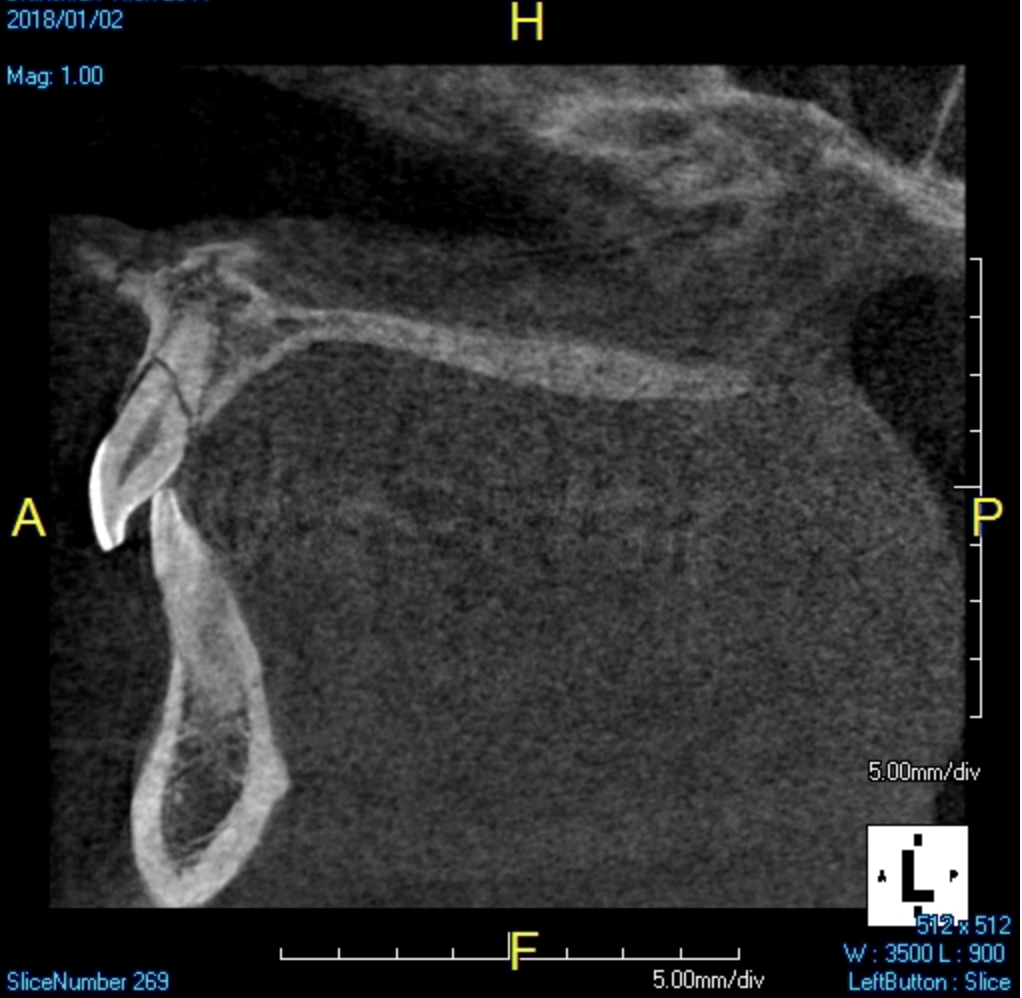

A young man presented with a fractured maxillary left-central incisor on a Monday morning after a Saturday evening discussion that did not end well (Figure 1). Visual oral examination and palpation of the structures revealed mobility of 3+, pain on palpation and percussion, a thick soft-tissue profile, and a low lip line. Gingival zeniths were irregular, there was a class II division 2 deep bite, and the periodontium was healthy overall (Figure 2 through Figure 4). Radiographs requested at the time of the initial visit were periapicals, panoramic, and CBCT images (Figure 5 and Figure 6). After all images and information were reviewed and the extent of his injury was discussed, the patient was presented with the following options: removable prosthetics, fixed partial denture, extract and do nothing, or extract and place a dental implant with bone augmentation.

Reviewing the CBCT images with the patient proved beneficial because he was able to clearly see the complete fracture of his tooth in the apical third of the root (Figure 6). Figure 5 represented what is a common radiograph in most dental offices, but it was not clear enough to diagnose a root fracture of this nature. The patient understood that the prognosis was poor and that the long-term restoration he wanted would mimic nature and be maintainable like natural dentition. The visual examination and photographs provided a basis for subsequent dental therapy and a definitive treatment plan for the future. The patient decided to move forward with tooth extraction, grafting, and immediate dental-implant placement with a screw-retained provisional out of occlusion.

Fig 6. Sagittal view of root fracture.

Figure 6